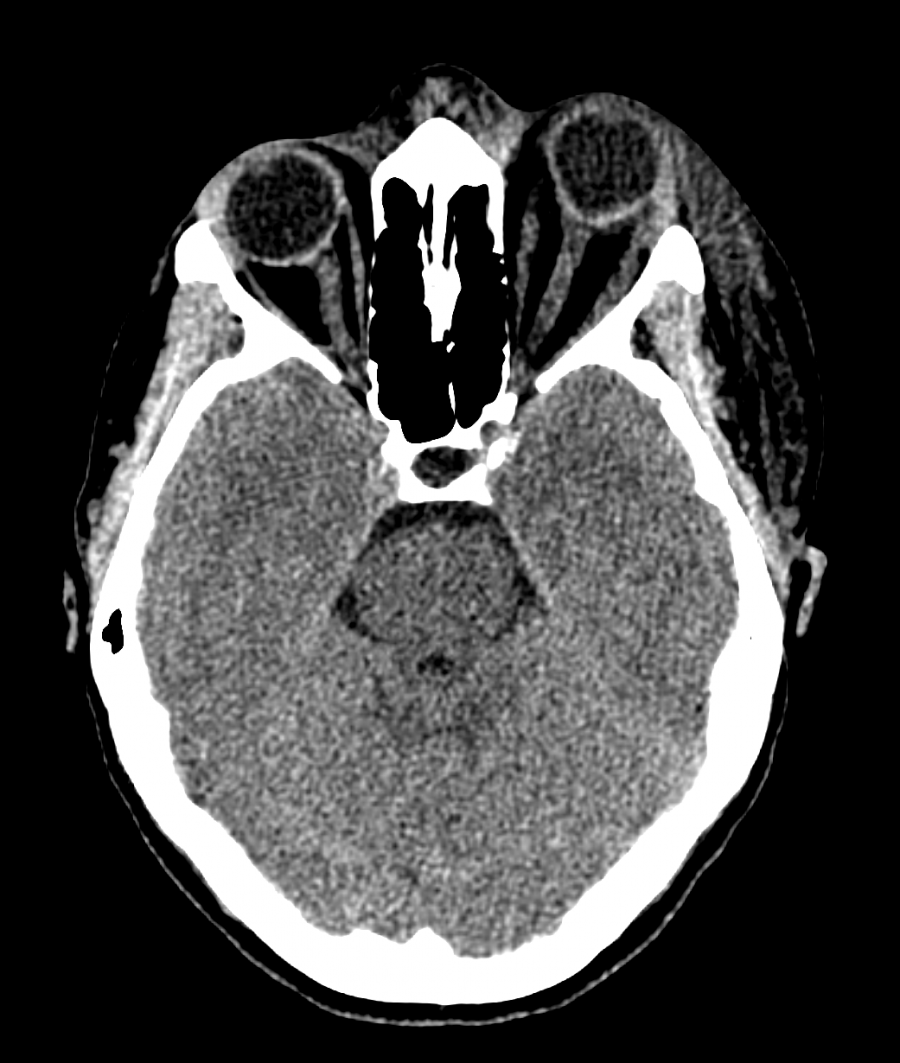

CT of the head and orbits should be obtained to rule out other etiologies, and it is classically notable for the presence of preseptal soft tissue swelling.

MRI with gadolinium may reveal engorgement of extraocular muscles and/or the lacrimal gland.[5] It may also demonstrate areas of intracerebral ischemia.[6][7] Examination of the macula will reveal retinal thickening with subretinal edema.[6]